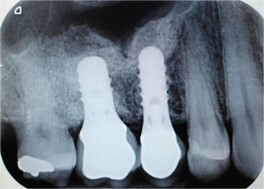

Il seno mascellare è uno dei quattro seni paranasali (seno sfenoidale, etmoidale, frontale e, appunto, mascellare) ed è morfologicamente il più voluminoso. I seni mascellari sono cavità situate all'interno delle ossa del cranio, sono rivestiti da mucosa respiratoria e comunicano tramite orifizi (chiamati osti) con le due cavità nasali. La perdita degli elementi dentali nel settore latero-posteriore dell’arcata superiore comporta un’atrofia dell’osso crestale e una lenta espansione della cavità sinusale. La richiesta del paziente di ripristinare in modo fisso i denti mancanti si scontra spesso con un ridotto o scarso volume osseo che rende necessaria la procedura chirurgica di rialzo del seno mascellare. In questi casi, infatti, non è possibile inserire in modo tradizionale gli impianti e si ha bisogno di volumi ossei più adeguati affinché gli impianti che vengono inseriti abbiano una lunghezza e un diametro sufficienti. Il termine "rialzo di seno" è dovuto proprio al fatto che i seni mascellari vengono spostati in alto dal ripristino dei volumi ossei, con materiali osteoconduttori, in modo da permettere un ancoraggio stabile degli impianti. Il posizionamento degli impianti è solitamente effettuato nell’ambito dello stesso intervento di rialzo del seno mascellare, in modo tale da ridurre il tempo globale di cura e protesizzazione. Il rialzo del seno mascellare si può eseguire con due tecniche: laterale o crestale. Con la prima tecnica si accede alla cavità del seno aprendo una piccola “finestra” ossea laterale procedendo cosi’ con visione diretta al riempimento della parte inferiore del seno mascellare. Nel rialzo del seno mascellare per via crestale invece si opera il rialzo del seno e il suo riempimento attraverso una piccola osteotomia crestale accedendo direttamente al seno a partire dalla cavità orale. Quest’ultima tecnica è sicuramente meno invasiva rispetto alla prima e il decorso post-operatorio è normalmente molto più rapido. Al fine di ridurre sempre piu’ l’invasività dell’atto chirurgico, in caso di osso crestale residuo di circa 5-6 mm, oggi e’ anche possibile ricorrere all’utilizzo di impianti corti che rappresentano una valida e predicibile alternativa al rialzo del seno mascellare.